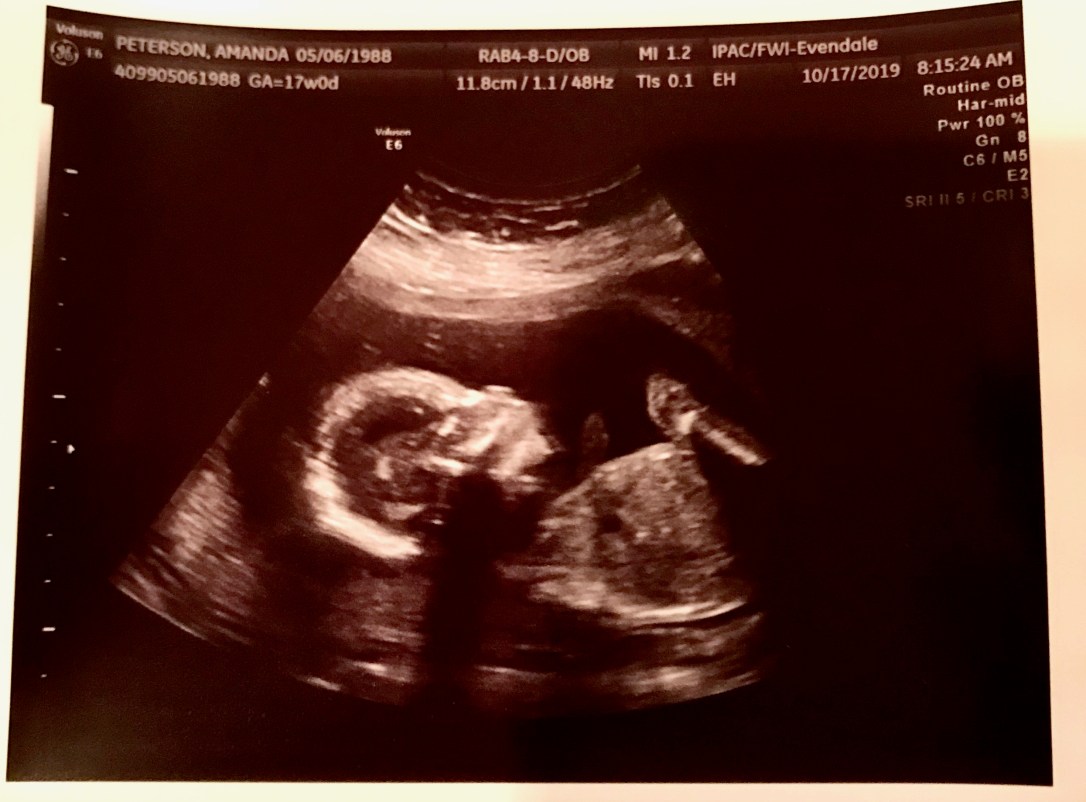

We had our third cervical ultrasound and hopefully the last! My cervix measured 3.8 cm., is fully closed and not funneling – all great things! Dr. LeMasters believes we are over that hump for now and surgery won’t be necessary, but they will continue to keep an eye on me as pregnancy progresses. We got to take a peek at the baby today too!

Sweet girl was all curled up and laying across my belly. Justin said, “OMG She sleeps like me!” with her hands folded on her chest, and we were cracking up about it. He seriously sleeps like someone just laid him in a coffin, with his hands folded on his chest. It’s bizarre!

She’s measuring perfectly, weighs 6 oz., and still has a super strong heartbeat. She’s the size of an onion this week, Daddy’s favorite! 🙂 (For those of you who don’t know us personally, Justin has an extreme hatred for onions!) We are so relieved and so thankful that baby is healthy! We’ll return in two weeks for the full anatomy scan, but the ultrasound tech saw her lady parts and confirmed what we already knew from the blood test – she is definitely a girl!